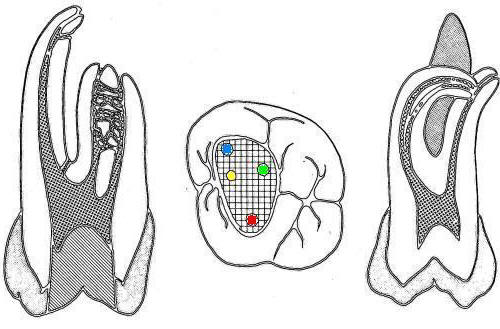

1º Molar Superior |

La flecha

amarilla indica un posible cuarto conducto. Debe

abrir hacia mesial para eliminar la pared

marcada en un circulo celeste, a la misma

profundidad que el conducto mesio-vestibular.

Ver imagen derecha. |

Entradas de los conductos que más frecuentemente

se hallan en los primeros molares superiores(1,2,23,27):

En fecha

reciente se ha incorporado a la clínica la

utilización del microscopio operatorio (MO)

El poder de

magnificación del MO con visión indirecta y

luz coaxial permite localizar las entradas

de los conductos calcificados. Incluso los

más pequeños y difíciles de ver como el

conducto mesio-palatino (Ver flecha amarilla

imagen superior izquierda)